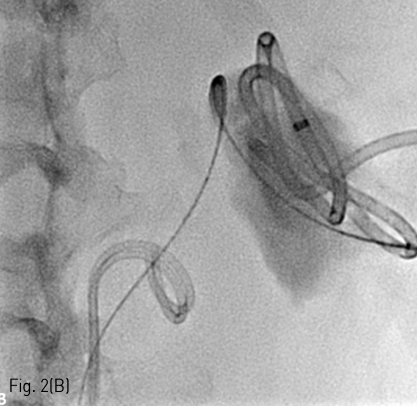

Fig 1A

(A) A 46-year-old female underwent partial nephrectomy for hypervascular mass (arrow) in right kidney.

조영 증강 복부 전산화 단층촬영에서 우측 신장에 renal cell carcinoma로 생각되는 약 3cm 크기의 hypervascular tumor가 있다 (Fig. 1A) 우측 신장 부분 절제술을 시행 받고 5일째 복통을 호소하여 시행한 복부 전산화 단층촬영에서 수술 부위 주변으로 large urinoma with contrast leakage를 확인할 수 있다 (Fig. 1B).